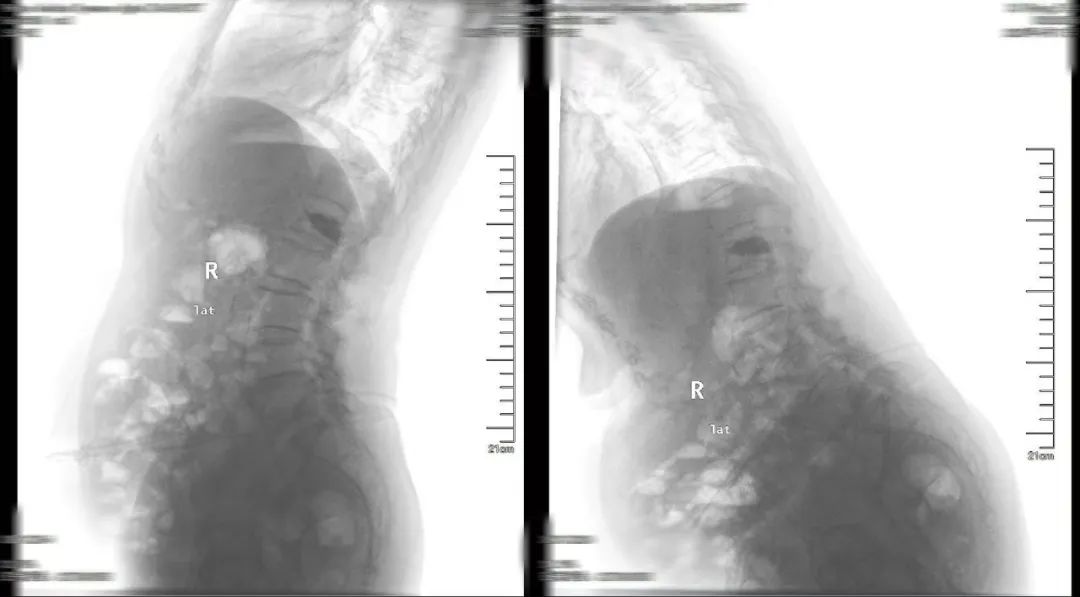

術前(qian)影像及診斷

MRI影(ying)像(xiang)檢查

L1椎(zhui)體成形術(shu)后,L4椎(zhui)體向前I°滑脫。

L4/L5椎(zhui)間盤(pan)膨出并右(you)后(hou)突。

L5/S1椎間盤膨出(chu)。